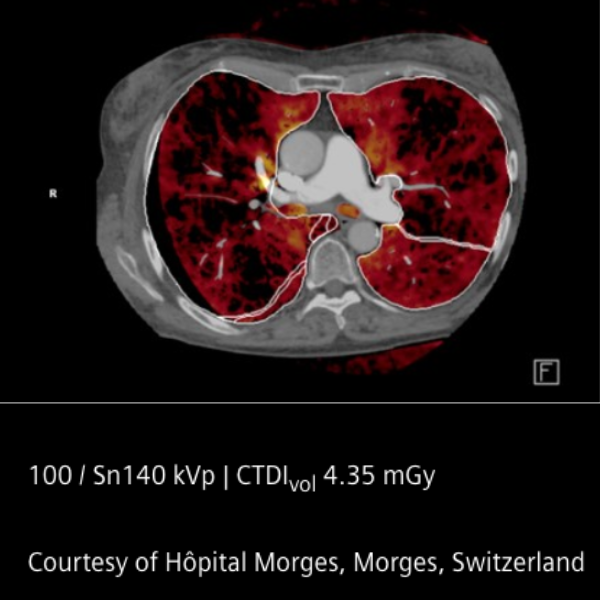

En el corazón del sistema se encuentran los detectores QuantaMax, capaces de medir cada fotón individualmente y convertirlo directamente en señal eléctrica. Esto permite eliminar el ruido electrónico, mejorar la relación contraste/ruido y obtener imágenes de alta resolución espectral sin aumentar la dosis de radiación. La combinación con la tecnología Dual Source y el potente tubo Vectron X-ray garantiza un rendimiento excepcional incluso en pacientes con alto índice de masa corporal.

El NAEOTOM Alpha ofrece velocidades de escaneo ultrarrápidas y una resolución temporal nativa de 66 ms, ampliando las posibilidades clínicas en cardiología, oncología, neurología y estudios complejos. Sus flujos de trabajo asistidos por inteligencia artificial optimizan la operación y apoyan la toma de decisiones clínicas.